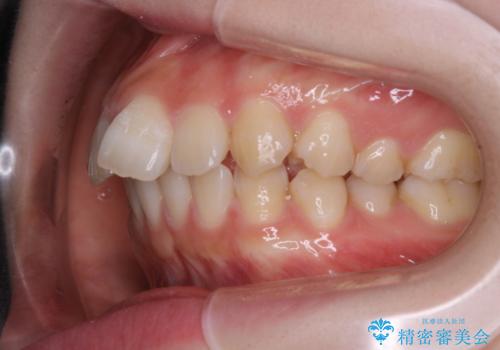

前歯の重なりは奥歯のズレが原因:まとめてインビザラインで治す

- 前歯の重なりが気になるとご相談にいらした方です。前歯のがたつきは奥歯の噛み合わせのズレが原因となっていたため、インビザラインFULLにて奥歯からしっかり治療していきました。

前歯のがたつきだけを治そうとした場合、噛み合わせは二の次なってしまう事が多く、せっかく綺麗になった歯並びも後戻りしやすくなります。

見た目だけでなく奥歯を移動させて噛み合わせの改善までが行えるのはインビザラインであるからこそです。奥歯の噛み合わせからしっかり機能させることで、長期間にわたって綺麗な歯並びを保ちやすくなります。